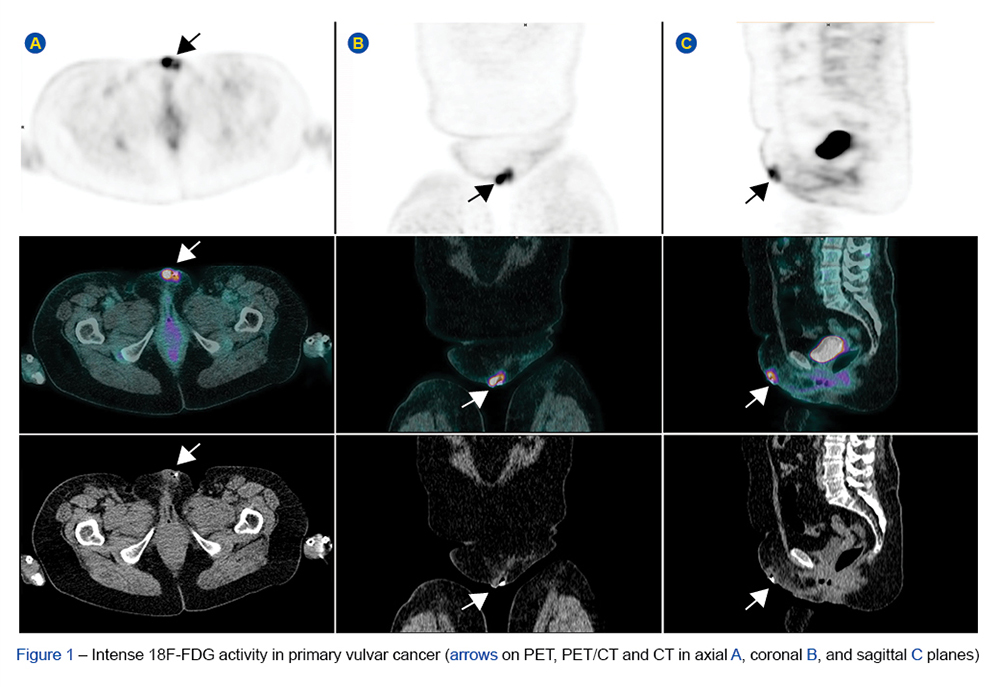

Inflammatory myofibroblastic tumour is a rare entity of indeterminate biological potential with a reduced tendency for recurrence and metastasis. Although it can arise...